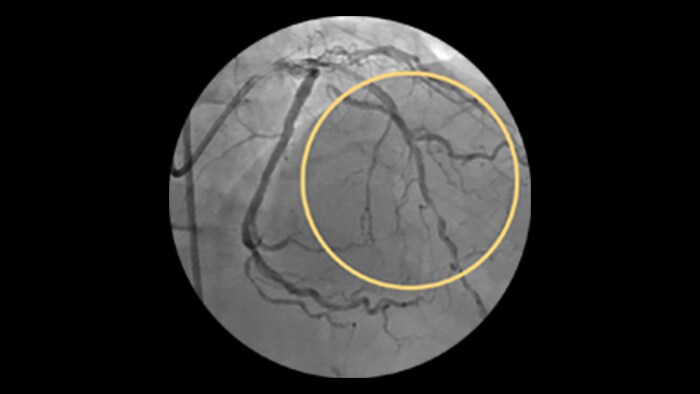

Saphenous vein graft and thrombus lesions

SVG patency rates have been reported at approximately 80% at 1 year and approximately 50% at 15 years and beyond.1

Advanced tools for optimal PCI outcomes